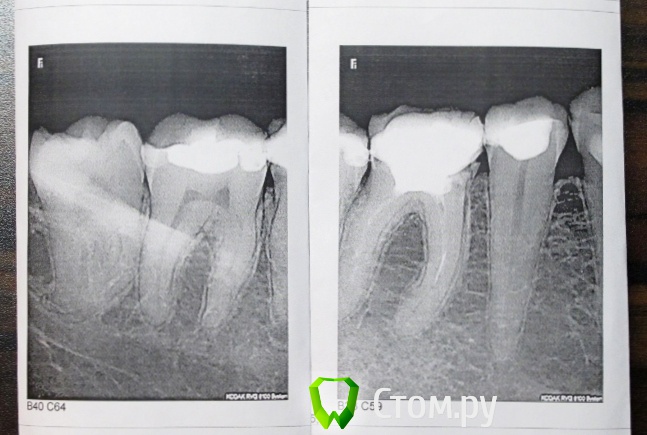

Stomart Опубликовано 16 января, 2014 Поделиться Опубликовано 16 января, 2014 6-й зуб надо перелечивать, 5-й проверить на витальность. Ссылка на комментарий

red_butler Опубликовано 16 января, 2014 Поделиться Опубликовано 16 января, 2014 +1 к последнему посту. Провести холодовую пробу эндофростом (специальный газ в болончике) 5 и 7 зубов, повторное лечение корневых каналов и протезирование 6-го, и удалить зуб мудрости Ссылка на комментарий

Maria2014 Опубликовано 16 января, 2014 Автор Поделиться Опубликовано 16 января, 2014 И еще вопрос - нужен ли микроскоп для перелечивания 6 зуба? Там же еще инструмент в канале. Ссылка на комментарий

DmitrySH Опубликовано 16 января, 2014 Поделиться Опубликовано 16 января, 2014 И еще вопрос - нужен ли микроскоп для перелечивания 6 зуба? Там же еще инструмент в канале. Нужен врач, который умеет работать с микроскопом. 1 Ссылка на комментарий

Maria2014 Опубликовано 2 февраля, 2014 Автор Поделиться Опубликовано 2 февраля, 2014 Здравствуйте.Пока ждала своей записи к врачу-эндодонтисту, боль сама собой прошла. Правда в том месте, где щека крепится к десне, между 6 и 7 появилось подвижное безболезненное (но с неприятными ощущениями) уплотнение, плоское, но в диаметре около 1,5 см.Этот самый врач на консультации сказал, что нужно перелечивать 6, а также он видит возможный пульпит в соседней 5 (по его мнению, описанная мной боль в челюсти больше соответствует пульпиту в 5). По поводу уплотнения он ответить затруднился, но возможно, это образовавшаяся после боли гранулема, которую не видно на снимке, т.к. она вышла в область мягких тканей.В ближайших планах перелечивание канала, но на текущий момент больше беспокоит это самое уплотнение. Бывают ли такие гранулемы, или что это вообще может быть и к кому обратиться? Ссылка на комментарий